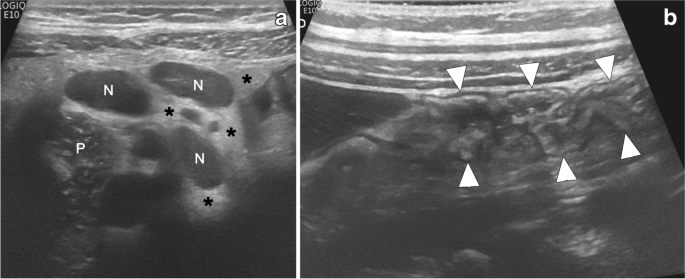

Open access: Ultrasonography in dermatologic surgery: revealing the unseen for improved surgical planning in

J Dtsch Dermatol Ges. Get it at the link: https://t.co/tO6OvT3NBKhttps://t.co/0IhXplVr6k@xworts @sonoskin @ecoalfageme

#skincancer #dermatologicultrasound #skintumor pic.twitter.com/QvYiZXvTLB— Ximena Wortsman (@xworts) May 26, 2022